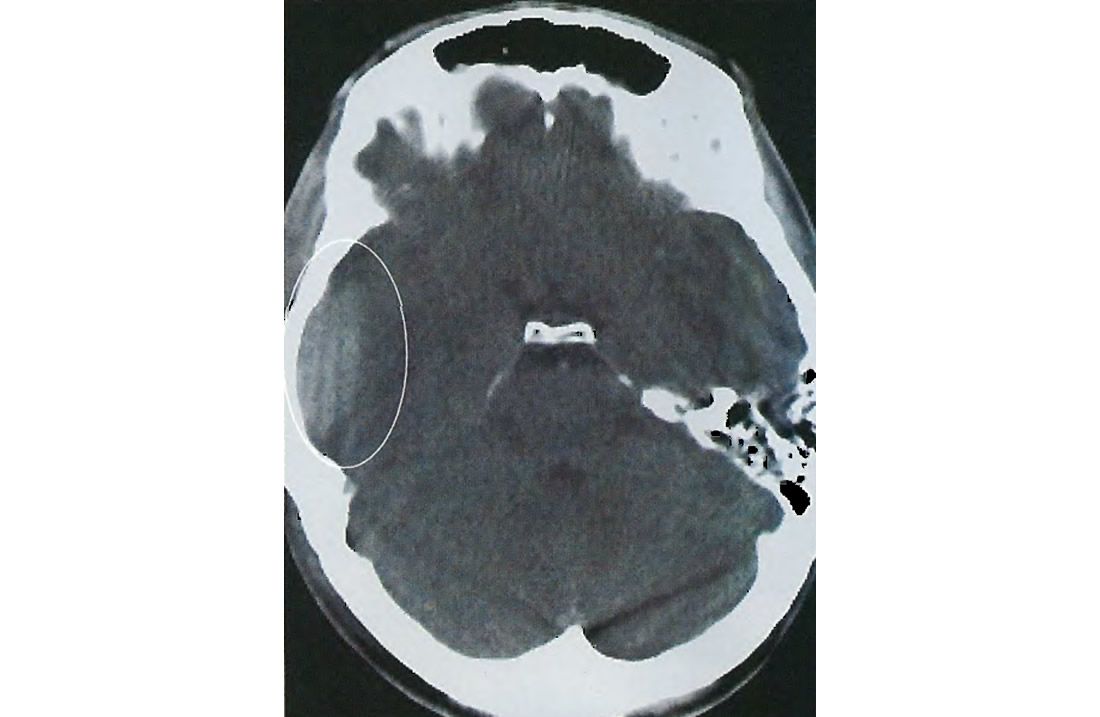

Иллюстрации и пояснения: гиподенсивный очаг на КТ головного мозга